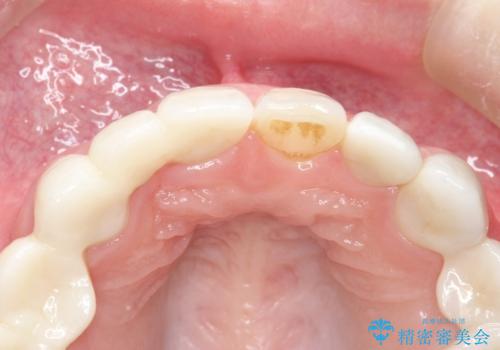

自然なオールセラミックへ変更することとなりました。

金属を使わないセラミックへ変更することで、自然な見た目になるとともに、ぴったりとした精度の高いかぶせ物を装着することができました。